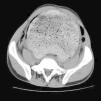

Enfermedad de Hirschsprung del adulto.

Figuras (2)